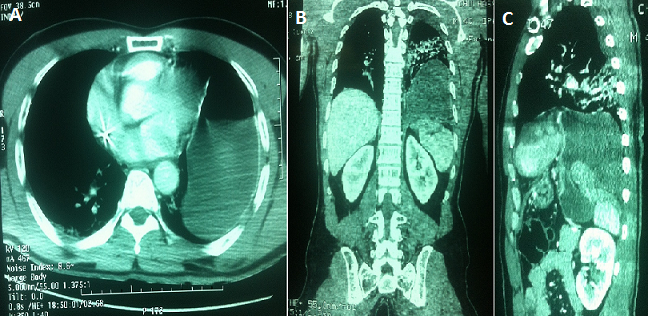

L'incidence des ruptures diaphragmatiques chez les patients admis à l'hôpital pour ‹‹traumatisme ferm雛 se situe entre 0,8% et 1,6%. Des lésions associées sont présentes dans 95% -100% des cas. Les ruptures diaphragmatiques surviennent principalement à gauche (68%-84%) et les structures le plus fréquemment herniées sont dans l'ordre décroissant: l'estomac, la rate, le côlon, l'intestin grêle et le foie. Seul 25%-40% des radiographies du thorax réalisées à l'entrée permettent le diagnostic et le CT-scan peut se révéler une aide précieuse. Dans la phase aiguë, ce sont les lésions associées qui déterminent le pronostic. L'approche chirurgicale consiste en une laparotomie ou laparoscopie seule dans la majorité des cas. Nous rapportons le cas d'un patient âgé de 50 ans, admis à notre hôpital pour la prise en charge d'un polytraumatisme, le scanner thoraco-abdominal réalisé dans le cadre du bilan lésionnel a objectivé une hernie diaphragmatique gauche post-traumatique. Le patient était opéré par voie d'abord médiane sus ombilicale, avec découverte d'une brèche diaphragmatique de 7 cm au niveau de la coupole gauche à travers laquelle l'estomac est ascensionné dans l'hémithorax gauche. Le traitement a consisté en une réduction de l'organe hernié avec suture de la brèche diaphragmatique et la mise en place d'un drain thoracique, les suites opératoire étaient simple et le patient a repris conscience a j11 de son admission en réanimation, il a quitté l'hôpital à j18.